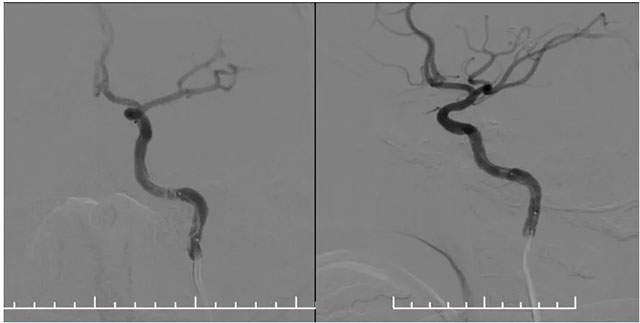

▲ 药物洗脱球囊在微导丝导引下到位于左侧椎动脉支架内,充分扩张药物球囊使其贴壁

▲ 球囊扩张后,支架内狭窄明显改善,支架贴壁良好

再次超选至左侧锁骨下动脉近椎动脉开口处,单次造影后明确开口狭窄程度,测量狭窄段长度及近远端血管直径,选取合适球囊。随后在微导丝辅助下通过支架内再狭窄段超选至左侧椎动脉V2段,选用2.5*15球囊,沿微导丝到位于狭窄段,球囊扩张至8atm,再次行椎动脉造影,血流有所改善。再次将球囊下移,球囊扩张至14atm,撤除球囊后行即刻造影示血流较前通畅。选择3.5*15药物洗脱球囊,超选至狭窄处,予以6atm,后撤除球囊,行即刻造影示血流较前明显改善,再次行椎动脉造影双侧大脑后动脉及基底动脉血流通畅。